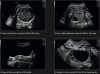

Yüksək keyfiyyətli 2D görüntüləmə

Speckle Reduction Imaging (SRI) – görüntü səs-küyünü azaldır

GE RAB2-6-RS (3D/4D Konveks)

GE RIC5-9W-RS (3D/4D Endokavitari)

Voluson P6 kompakt və yüksək performanslı ultrasəs sistemidir, rutin ginekoloji və obstetrik müayinələr üçün idealdır. Yüksək keyfiyyətli 2D görüntüləmə və 3D/4D imkanları təqdim edir, dəqiq nəticələr əldə etməyə imkan verir. 17 düymlük yüksək çözünürlüklü LCD ekran və üç aktiv prob portu ilə məkan məhdudiyyəti olan klinikalar üçün ideal seçimdir. Voluson P6 CrossXBeamSpeckle Reduction Imaging (SRI) kimi texnologiyaları birləşdirərək, aydın və detallı görüntülər təqdim edir.